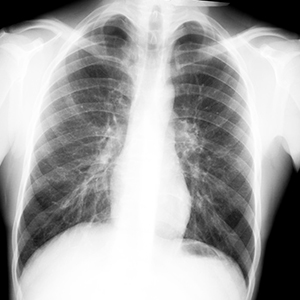

Для того, чтобы не допустить развития запущенных форм туберкулеза, в нашей стране все взрослые и подростки 15 лет и старше 1 раз в 2 года обязательно проходят флюорографию или рентгенологическое обследование легких.

Профилактикой туберкулеза во взрослом возрасте является ежегодное диспансерное наблюдение и выявление заболевания на ранних стадиях. С целью выявления туберкулёза на ранних стадиях взрослым необходимо проходить флюорографическое обследование в поликлинике не реже 1 раза в год (в зависимости от профессии, состояния здоровья и принадлежности к различным группам риска). Чтобы избежать этого коварного заболевания, следует повысить сопротивляемость организма, вести здоровый образ жизни, который включает рациональное питание, отказ от вредных привычек, занятие физкультурой, спортом, закаливание своего организма.

Туберкулез – инфекционное заболевание, вызываемое различными видами микобактерий – Mycobacterium tuberculosis (палочка Коха). Туберкулез обычно поражает легкие, реже затрагивает другие органы и системы (кости, суставы, мочеполовые органы, кожу, глаза, лимфатическую систему, нервную систему). При отсутствии лечения заболевание прогрессирует и заканчивается летально. Наряду с человеком, туберкулезом могут быть инфицированы и животные (крупный рогатый скот, грызуны, куры и др.).